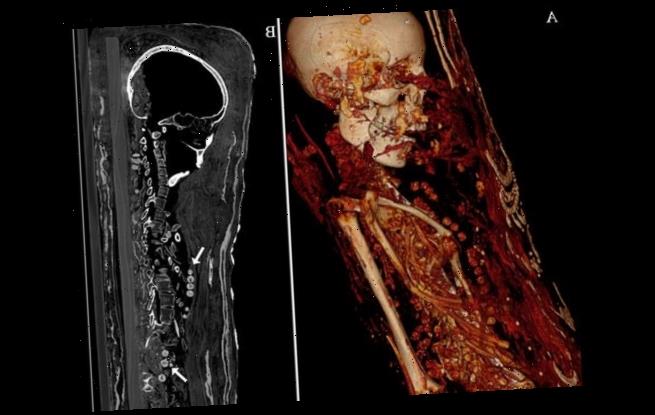

Archaeologists from the Reiss Engelhorn Meuseu, Germany, had to use CT scans to reveal the inside of the plaster coating – rather than risk damaging the remains.

Archaeologists from the Reiss Engelhorn Meuseu, Germany, had to use CT scans as, unlike other mummies, the bodies were coated in a hard plaster shell – not wood

At least one of the three mummies had been buried with their organs – including the brain – and both females were wearing necklaces, according to the researchers.

CT scans revealed the mummies had been interred with items thought to be useful in the afterlife, including coins designed to pay for passage across the River Styx.

All three of the mummies had medical problems, as revealed by the CT scans – from arthritis to a tumour and all of them died at relatively young ages.

The man died between the ages of 25 and 30, was about 5ft 4in and some of his bones were broken and jumbled – possibly due to someone trying to unwrap him.

His brain was not preserved but there was ‘no evidence it had been removed through his nose’ as is usually the practice for mummification, authors wrote.

‘We are quite sure there was no removing the brain or the internal organs’ from these mummies, Zesch told LiveScience.

The man died between the ages of 25 and 30, was about 5ft 4in and some of his bones were broken and jumbled – possibly due to someone trying to unwrap him

At least one of the three mummies had been buried with their organs – including the brain – and both females were wearing necklaces, according to the researchers